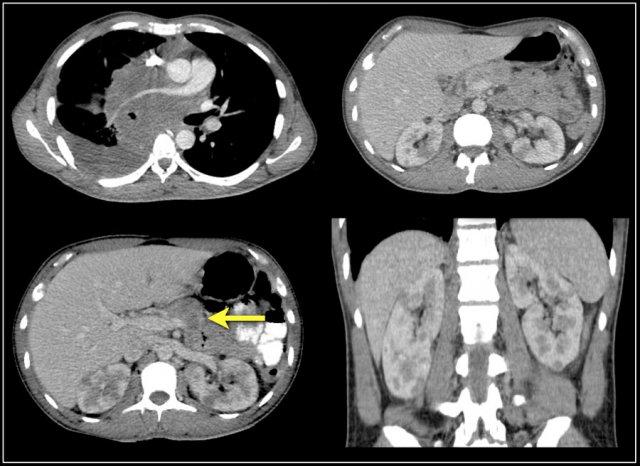

Tổn thương thâm nhiễm ở cực trên thận phải, hầu như không thấy trên ảnh không tiêm thuốc (bên trái), thấy rõ ràng ở thì thận (bên phải). Giải phẫu bệnh xác nhận RCC tế bào sáng

Trong số tất cả các RCC tế bào sáng, khoảng 5% có kiểu tăng trưởng thâm nhiễm.

Mặc dù đây chỉ là một tỷ lệ nhỏ trong số các RCC, nhưng tần suất chung của RCC khiến đây trở thành một chẩn đoán phân biệt quan trọng đối với tổn thương thâm nhiễm dạng hình đậu (bean-type).

RCC thâm nhiễm có tính chất xâm lấn cao và tăng sinh mạch máu.

Tổn thương làm thay đổi cấu trúc nội tại của thận nhưng vẫn bảo tồn đường bờ thận. Các bất thường hệ thống đài bể thận có thể tương tự như những gì thấy trong ung thư biểu mô tế bào chuyển tiếp (transitional cell carcinoma).